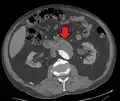

three white arrows pointing to an enlargement of the abdominal aorta

CT reconstruction image of an abdominal aortic aneurysm (white arrows)